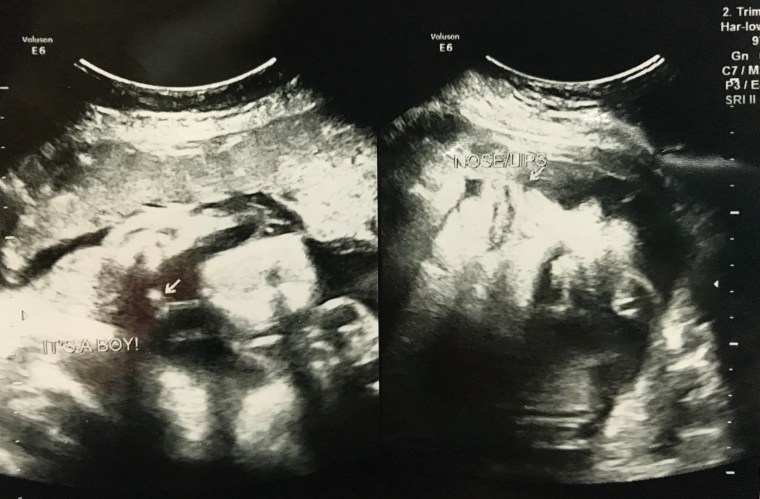

I was scheduled for a congenital anomaly scan for this month. Even though I was feeling a bit worried, I stayed positive and let God be in control of everything. My first born Matteo (now an angel in heaven), suffered from congenital heart disease, which we didn’t know until he was born.

The scan went well, I was able to see those tiny hands and feet. All of his body parts and organs were well developed, and the heart, where my doctor focused more, was pumping perfectly. As for the gender, we decided to hold it off since one of my friends planned to throw a gender reveal party, which happened a week after the scan.

“It’s a Baby Boy. Tep and I didn’t expected it. All along we thought that it would be a baby girl because of my severe symptoms.